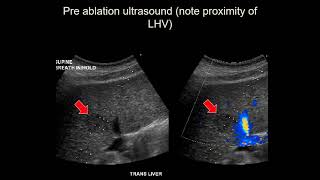

Image guided tumor ablation Image Guided Tumor Ablation, L Hinshaw, MD

Image Guided Tumor Ablation, L Hinshaw, MD Image-guided Ablation

Image guided tumor ablation Image Guided Tumor Ablation, L Hinshaw, MD

Image Guided Tumor Ablation, L Hinshaw, MD Image-guided Ablation